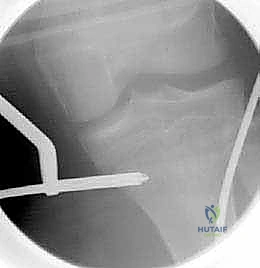

- استخدام جهاز الأشعة القوسي (C-Arm Fluoroscopy): يُستخدم هذا الجهاز المتطور طوال العملية لتوفير صور أشعة حية ومباشرة، مما يسمح للدكتور هطيف برؤية العظم من الداخل دون الحاجة لشقوق جراحية كبيرة.

- تقنية التدخل المحدود (Minimally Invasive): في حالة استخدام المسامير المرنة (TENs)، يتم عمل شقين صغيرين (حوالي 1-2 سم) بالقرب من الركبة أو الكاحل.

- تمرير المسامير والتثبيت: يتم إدخال المسامير المرنة بمهارة فائقة داخل تجويف العظم وتوجيهها لتتجاوز منطقة الكسر، مما يعيد العظم إلى استقامته الطبيعية ويثبته بقوة.

- الإغلاق والتأكد: يتم التأكد من ثبات الكسر وحركة المفاصل المجاورة. تُغلق الشقوق الصغيرة بغرز تجميلية، وتوضع جبيرة خفيفة لحماية الساق في الأيام الأولى.